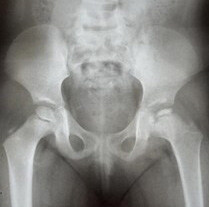

Results: We studied 20 patients with Meyer's dysplasia, representing 1.4% of LCPD cases in children. The majority were boys (85%) with symptom onset at 38 months. Claudication (25%) and mild pain (40%) were the main complaints. Radiographic findings showed a smaller, granular, or asymmetric nucleus. The average follow-up was 6.4 years, with interventional treatment in 5 cases. Most showed complete reossification and centralization of the femoral head.

Abstract Image